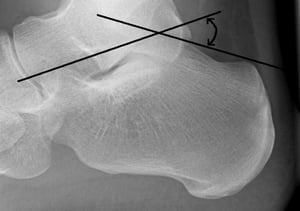

Böhler-Winkel

Der Bohler-Winkel wird durch den Schnittpunkt einer Linie vom Oberrand der hinteren Fersenbeinhöcker an der übergeordneten subtalaren Gelenkfläche und einer Linie von der oberen subtalaren Gelenkfläche zum Oberrand des vorderen Kalkaneus-Prozesses gebildet. Normalerweise beträgt der Winkel 20 bis 40°. Ein Winkel von

Image courtesy of Danielle Campagne, MD.

Der Böhler-Winkel wird auf dem seitlichen Röntgenbild bestimmt. Dieser Winkel wird durch den Schnittpunkt einer Linie vom Oberrand der hinteren Fersenbeinhöcker an der übergeordneten subtalaren Gelenkfläche und einer Linie von der oberen subtalaren Gelenkfläche zum Oberrand des vorderen Kalkaneus-Prozesses gebildet. Normalerweise beträgt der Winkel 20 bis 40°. Ein Winkel von < 20° deutet auf eine Fraktur hin.